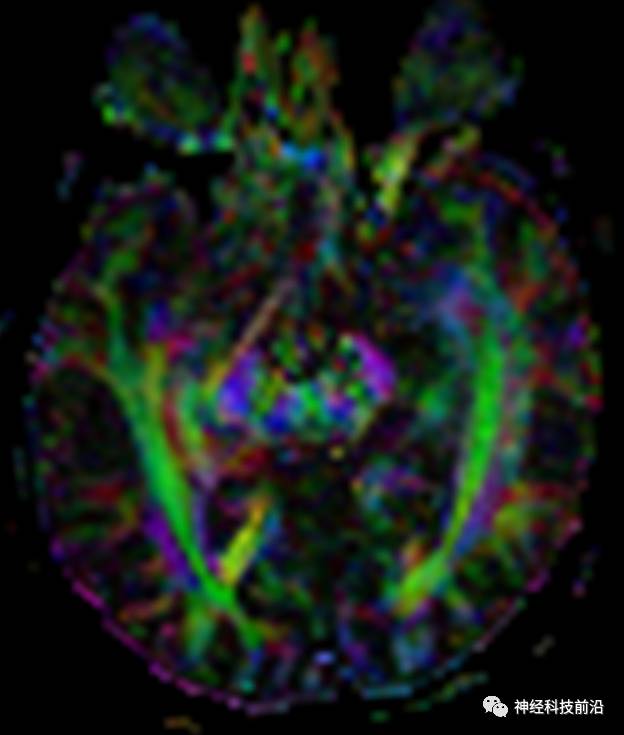

DTI原始图像